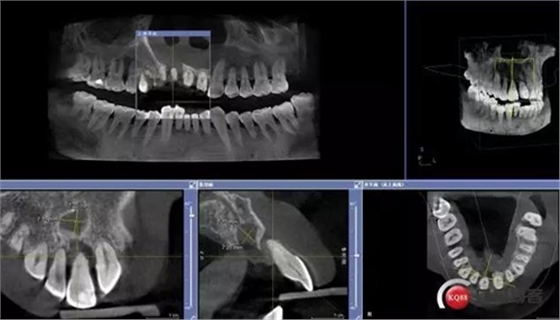

患者:王XX 年齡:42 上前牙松動(dòng)數(shù)年,從未做過任何處理,今來院就診;檢查:CBCT示上前牙區(qū)顎側(cè)一大小約7x7mm囊腫;治療計(jì)劃:即刻種植同期摘除囊腫

術(shù)前CBCT